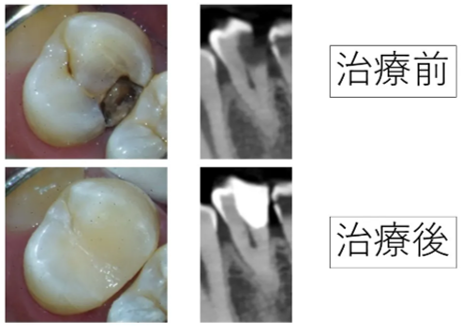

神経を取ると言われた深い虫歯をVPTで神経を残した症例

歯に黒い線。大きな虫歯でも神経を残せた症例|生活歯髄保存療法